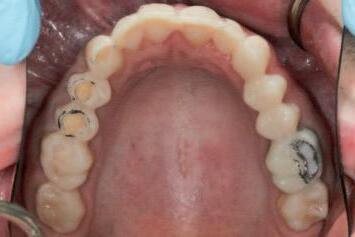

n Tooth structure is reduced until it conforms precisely to the contours of the preparation guide. The removal of the contrasting marker ink, caused by direct contact with the rotating diamond bur, indicates that the target reduction depth has been achieved. This visual endpoint ensures accurate, conservative preparation aligned with the contours of the planned definitive

(

restoration

Figure 4).

FIGURE 4: The appearance of the guide following the tooth reduction procedure. The clinician should stop the procedure the moment the contrasting ink has been displaced.

A C B

FIGURE 5: Evaluation of the clinical situation before and after the planned tooth reduction, highlighting the subtle and conservative but clinically meaningful changes that have been made, prior to tooth preparations for indirect restorations.

n Upon removal of the tooth reduction guide, a subtle, conservative but clinically meaningful elimination of anticipated interferences may be confirmed (Figure 5). The guided reduction procedure has simplified the subsequent process of tooth preparation for indirect restorations, at the next step of the treatment plan.